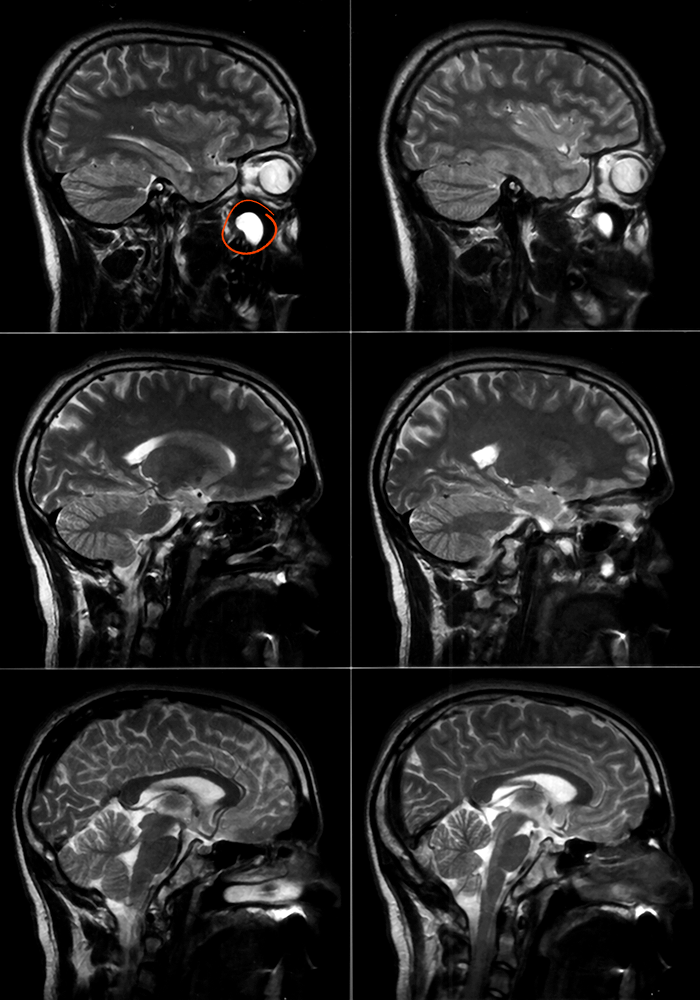

Upper left one, the big white thing under my eye: